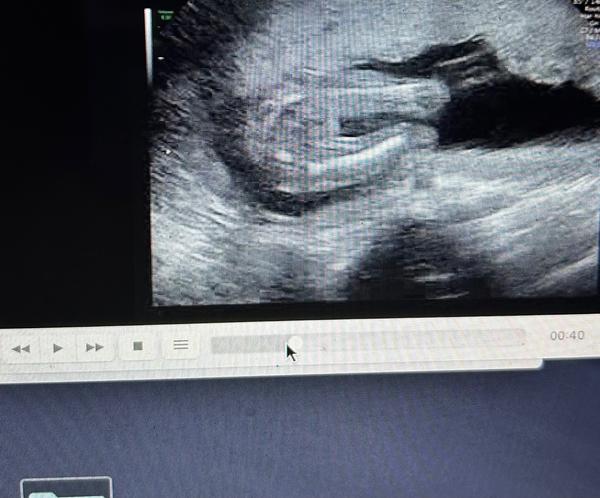

chtěla bych se zeptat na pohlaví miminka. 🙂

z fotografií nelze jednoznačně říci. ☹ Výpovědní hodnotu vyšetření "naživo" fotografie nedokáží nahradit.